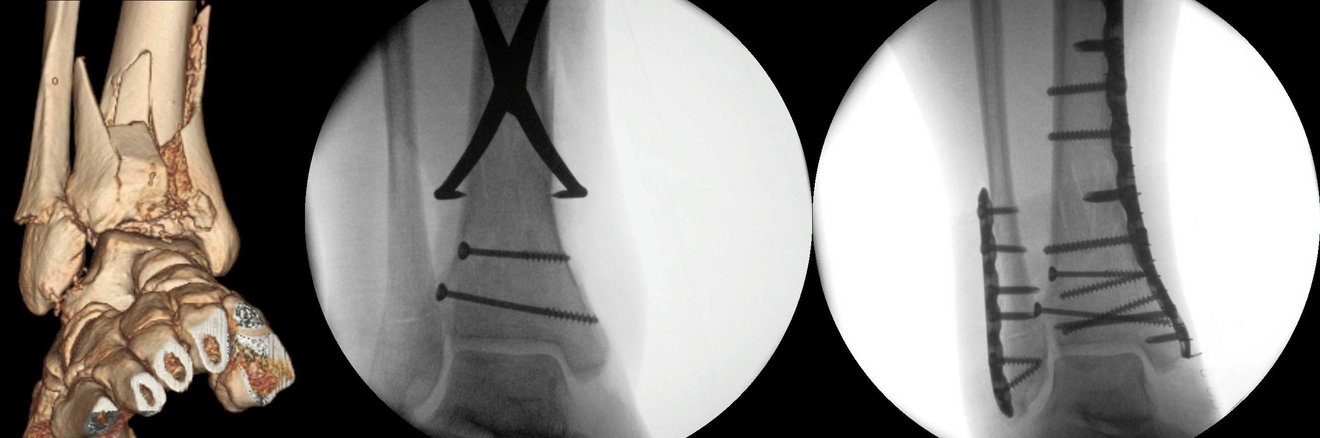

Bei der Versteifung werden die Zehenknochen in Korrekturstellung durch gekreuzte Schrauben oder Drähte, Platten oder Klammern fixiert. Die Entfernung des Gelenkes stellt nur in Einzelfällen eine sinnvolle Lösung dar. In jüngerer Zeit gewinnt der prothetische Ersatz des Großzehengrundgelenks zunehmend an Bedeutung. Dabei werden entweder beide gelenkbildenden Knochen oder nur der erste Mittelfußknochen durch einen Oberflächenersatz erneuert.

Sind weder ein Gelenkerhalt noch eine Prothesenimplantation möglich, steht eine Versteifungsoperation (Arthrodese) asl Alternative zur Verfügung. Nach Entfernung des Restknorpels werden dabei Schienbein und Sprungbein fest miteinander verbunden. Dieser Eingriff wird in unserer Klinik bevorzugt in minimalinasiver Technik durchgeführt.

Bei einer fortgeschrittenen, schmerzhaften Arthrose des unteren Sprunggelenks kommt nur eine Versteifung des Gelenks in Frage. Allerdings ist hier der Verlust an Beweglichkeit geringer als beim oberen Sprunggelenk, so dass die Versteifung beim Gehen kaum störend auffällt. Sprungbein und Fersenbein werden für die Versteifung mit Schrauben fixiert.